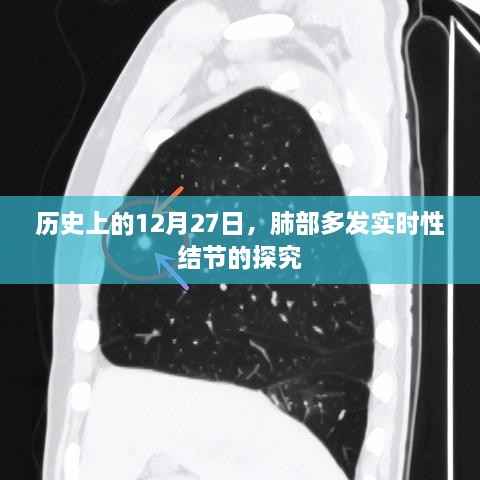

肺部多发实时性结节,简称肺结节,是指肺部出现的直径小于或等于3cm的类圆形或不规则形的高密度影,大多数肺结节是良性的,但部分结节可能是肺癌的早期表现,随着医学影像学的发展,肺结节的检出率逐年上升,已成为临床关注的焦点之一。

1、新型影像技术:高分辨率CT、MRI等影像技术的不断发展,为肺结节的准确诊断提供了有力支持。